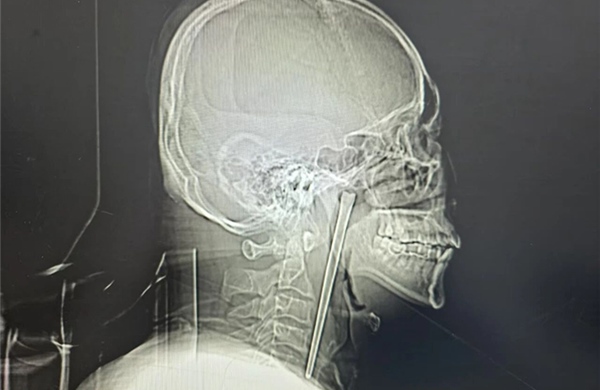

Một người đàn ông ở Đại Liên (Trung Quốc) đã sống suốt 8 năm với một chiếc đũa kim loại dài mắc trong cổ họng, trước khi được các bác sĩ phẫu thuật lấy ra an toàn.